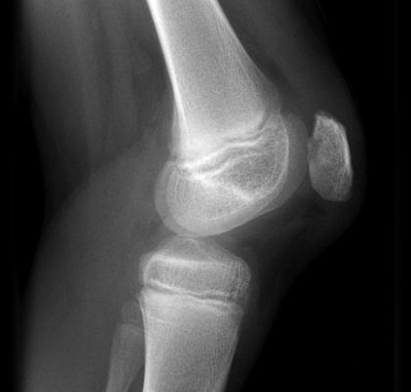

La condromalacia rotuliana es una afección ortopédica que afecta el cartílago en la parte posterior de la rótula, conocido como patela. Este cartílago es fundamental para el funcionamiento óptimo de la articulación de la rodilla, ya que permite un deslizamiento suave entre la rótula y el fémur durante el movimiento. Cuando este cartílago se desgasta o se daña, puede llevar a una serie de síntomas que incluyen dolor, inflamación y rigidez en la rodilla. A menudo, las personas experimentan molestias durante actividades cotidianas que requieren flexionar la rodilla, como caminar, subir escaleras, o agacharse.

Las lesiones anteriores también juegan un papel significativo en el desarrollo de esta afección. Una lesión en la rodilla, como un esguince o una fractura, puede alterar el funcionamiento normal de la articulación y provocar cambios en la alineación de la rótula. Cuando la rótula no está correctamente alineada, se genera un roce anómalo entre el cartílago y el hueso, lo que puede contribuir al deterioro del cartílago y ocasionar condromalacia. Es fundamental considerar tanto las lesiones agudas como las lesiones crónicas, ya que ambas pueden tener un impacto a largo plazo en la salud de la rodilla.

Otro síntoma característico relacionado con la condromalacia rotuliana es el chasquido al mover la rodilla. Este ruido o sensación puede ser el resultado del roce de la rótula contra el fémur debido al desgaste del cartílago. Esta inestabilidad en la articulación puede llevar a un incremento del dolor si no se maneja adecuadamente. En situaciones donde se realiza actividad física intensa, como correr o practicar deportes de impacto, estos síntomas pueden agravarse, haciendo que sea crucial prestar atención a las señales que el cuerpo envía.